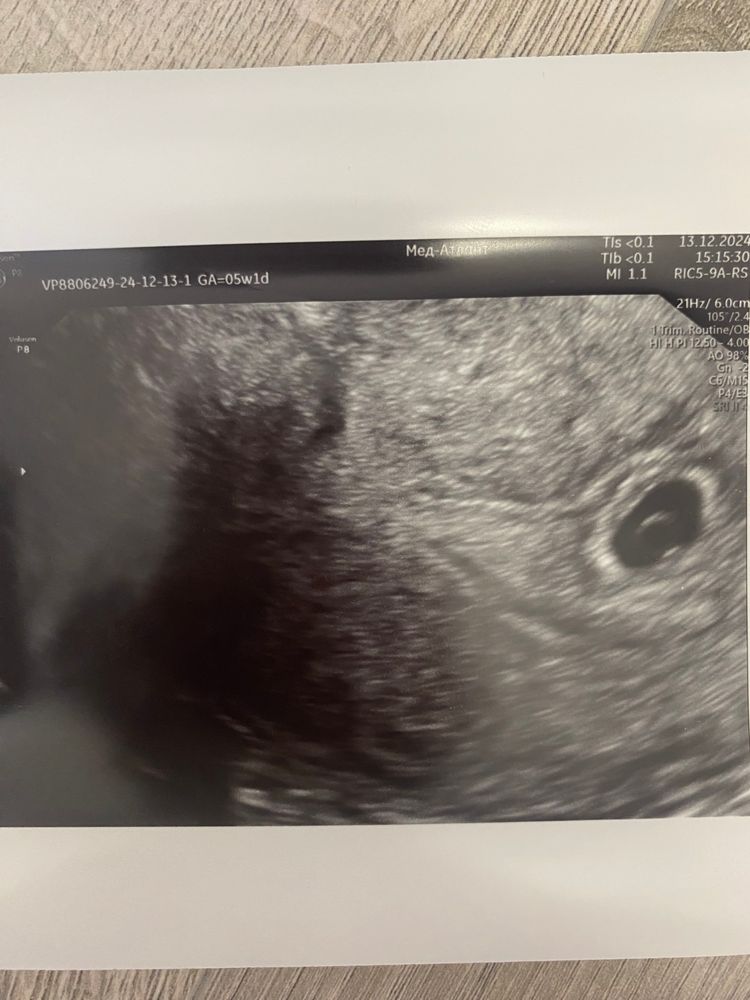

Здесь 5 недель и 1 день